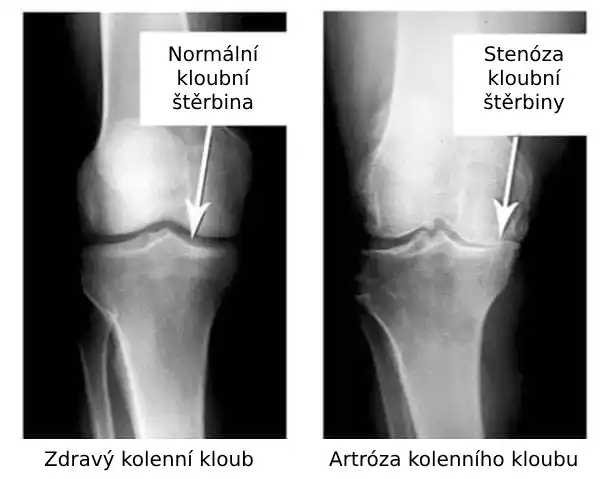

Podívejte se na tyto obrázky, můžete vidět, že na obrázku vpravo není žádný kloubní prostor, kosti se o sebe třou a způsobují silnou bolest. A tento proces je velmi těžké zastavit! Za pár let se ten člověk stane invalidním a už se nebude schopen sám živit.

Markéta Svobodová: Především jsou to vážná zranění a napětí. Nadváha také hodně zatěžuje vaše klouby. Sedavý způsob života, stres, nadbytek soli a cukru ve stravě, to vše změkčuje chrupavčitou tkáň, opotřebovává ji a ředí. Při každém novém pohybu se chrupavka ničí a deformuje a kosti se o sebe začnou třít, což způsobuje nesnesitelnou bolest.

Nežertujte s artrózou a artritidou! Onemocnění kloubů vás posadí na invalidní vozík za necelé 3 roky!